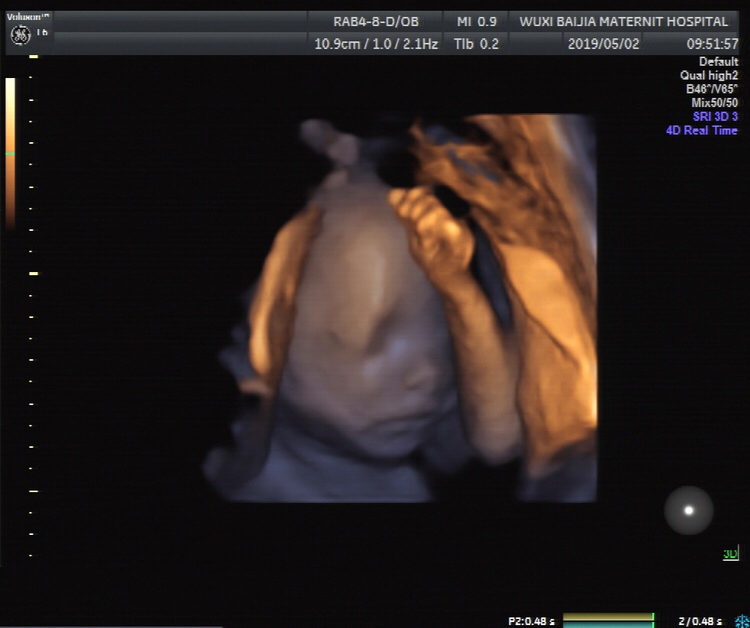

孕25周+4天

孕25周+3天

哈哈,我也是,四维的单子长得太像男宝了,但是照了B超,女宝宝

HYGJhwab[帖主]:生出来就可爱了 四维顶多能看出来像谁